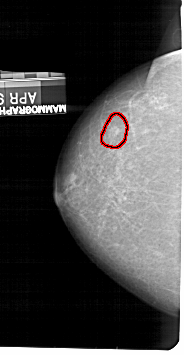

A_1435_1.RIGHT_MLO

RIGHT_MLO LINES 5326 PIXELS_PER_LINE 2851 BITS_PER_PIXEL 12 RESOLUTION 43.5 OVERLAY

FILE: A_1435_1.RIGHT_MLO.OVERLAY

TOTAL_ABNORMALITIES 1

ABNORMALITY 1

LESION_TYPE MASS SHAPE OVAL MARGINS ILL_DEFINED

ASSESSMENT 4

SUBTLETY 4

PATHOLOGY BENIGN

TOTAL_OUTLINES 1

BOUNDARY